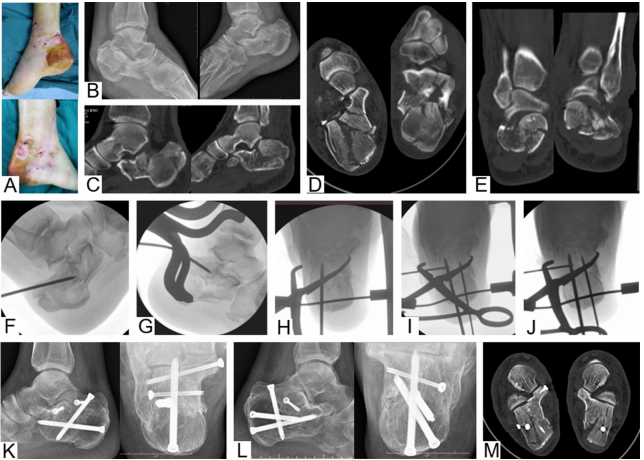

图 3. 该病例显示一名双侧舌型DIACFs患者接受三步复位治疗。(A) 术后外观显示对肿胀的软组织干扰极小。术前侧位(B)、矢状位(C)、水平位(D)和冠状位(E)视图显示双侧骨折均应归类为Sanders III型骨折。在第一和第二步中,在双侧牵引器的帮助下,插入一根斯氏针到主要舌型骨折块中进行撬拨(F, G)。在第三步中,通过非对称钳和几根从足底或跟骨外侧壁导向关节骨折块的克氏针在透视下的配合,实现了距下后关节面的复位(H-J)。术后图像显示双侧骨折愈合,复位满意(K-M)。